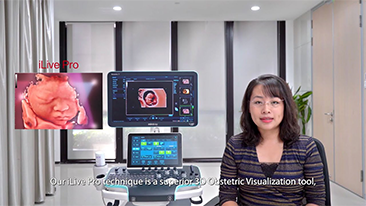

Meno stetoscopio e pi├╣ ultrasuoni?

L'ottimizzazione dei flussi di lavoro in ambito ostetrico e ginecologico ├© necessaria per completare grandi volumi di visite di screening per la salute delle donne. Ad esempio, le malformazioni del sistema nervoso centrale (SNC) sono una delle anomalie congenite pi├╣ comuni. A causa di varie circostanze che limitano l'accuratezza delle immagini, come la posizione poco adeguata del feto, l'MSP ├© particolarmente difficile da rilevare tramite l'ecografia 2D. Pertanto, il rilevamento e le misurazioni automatizzate possono migliorare notevolmente l'efficienza della scansione.